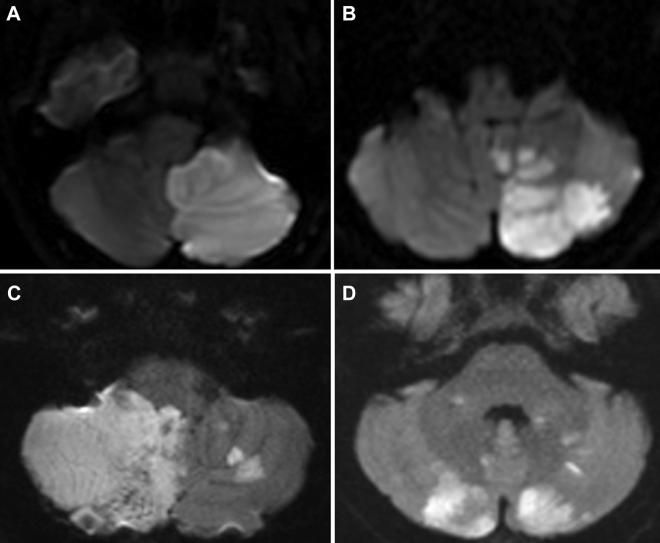

We reported that 4 patients who were healthy at baseline developed transient cardiac stunning after acute ischemic cerebellar stroke. Patients' electrocardiograms and cardiac enzyme levels were normal, and no cardiac intervention was performed because of the presumed neurogenic cardiac outcome. Their cardiac dysfunction spontaneously returned to normal range within 2 to 3 months, as demonstrated by repeated cardiac magnetic resonance imaging or echocardiography.

Although acute stroke involving the insular cortex is a common cause of cardiac stunning, strokes of other territories, such as cerebellar stroke, as shown in this case series report, can also cause neurogenic cardiac dysfunction and should not be overlooked.